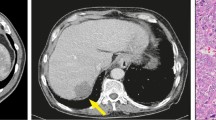

The software-assisted planning of radiofrequency-ablation of liver tumors calls for robust and fast methods to segment the tumor and surrounding vascular structures from clinical data to allow a numerical estimation, whether a complete thermal destruction of the tumor is feasible taking the cooling effect of the vessels into account. As the clinical workflow in radiofrequency-ablation does not allow for time consuming planning procedures, the implementation of robust and fast segmentation algorithms is critical in building a streamlined software application tailored to the clinical needs. To suppress typical artifacts in clinical CT or MRT data - like inhomogeneous background density due to the imaging procedure - a Bayesian background compensation is developed, which subsequently allows a robust segmentation of the vessels by fast threshold based algorithms. The presented Bayesian background compensation has proven to handle a wide range of image perturbances in MRT and CT data and leads to a fast and reliable identification of vascular structures in clinical data.